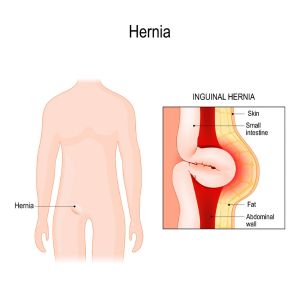

Inguinal Hernia